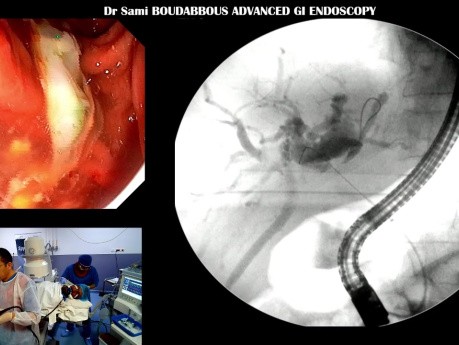

CPRE pour Angiocholite Aigüe Hydatique

Cas clinique: Cholangite aiguë liée à un kyste hydatique du foie avec fistule biliaire.